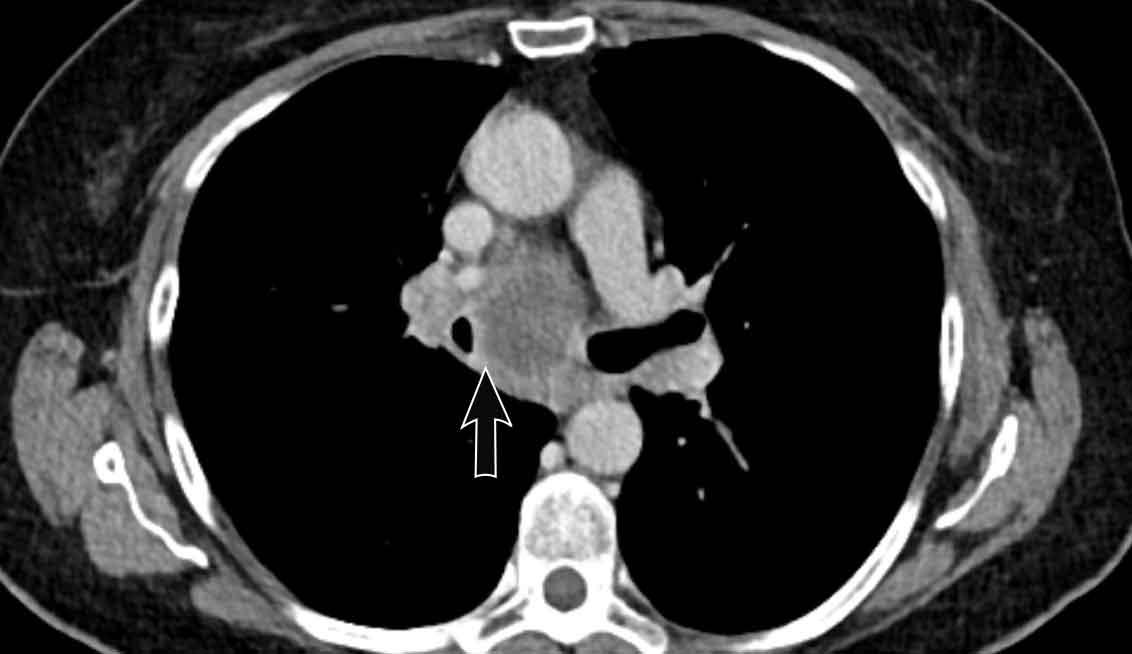

Hình ảnh

Viêm trung thất xơ hóa bên phải ở nam giới 51 tuổi, cho thấy tổn thương tỷ trọng mô mềm xung quanh phế quản chính phải (mũi tên).

Cùng bệnh nhân.

Có các dấu hiệu thứ phát của chèn ép đường thở trung tâm và mạch máu, với mất thể tích phổi khu trú và dày mô kẽ do phù nề.